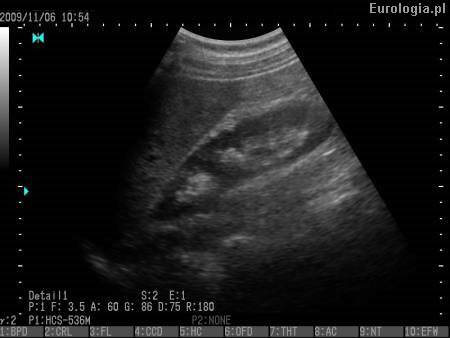

Fot. USG jamy brzusznej - prawidłowy obraz prawej nerki.

Piramida nerkowa jest częścią strukturalną rdzenia nerki. Nazwa pochodzi od kształtu przypominającego piramidę. Na szczycie każdej piramidy znajduje się brodawka nerkowa, którą mocz spływa do układu kielichowo miedniczkowego. Piramidy nerkowe zbudowane są z kanalików nerkowych i występują w liczbie 10 - 20 w każdej z nerek.

Lekarz wykonujący badanie USG powinien dać Pani jasną odpowiedź co dalej robić z takim obrazem piramidy nerkowej. W większości przypadków zaleca się USG kontrolne po kilku miesiącach lub tomografię komputerową celem różnicowania przerośniętej piramidy z guzem nerki. Dodatkowo polecamy przeczytanie artykułu: Przerost piramidy nerkowej czy guz nerki.